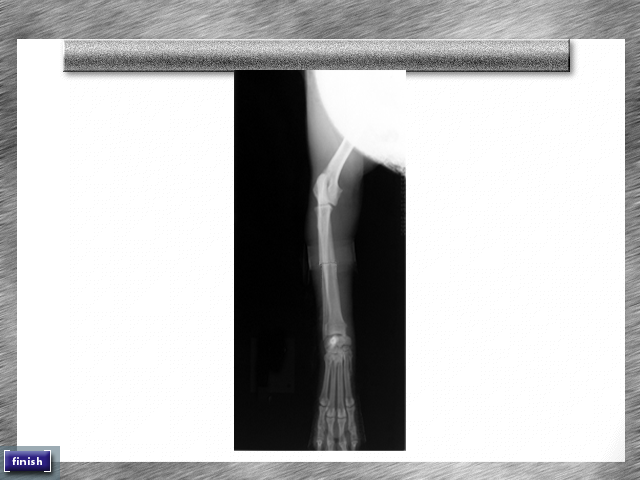

Visually, Vet Emergency 2 takes a practical, clear approach. The game opts for functional, clean 2D graphics rather than flashy 3D environments, ensuring that each tool, patient, and machine is easily identifiable. While the textures are simple, they’re crisp enough to convey important details, such as fracture lines on an X-ray or the subtle color changes in an animal’s skin indicating illness. This clarity supports gameplay by reducing visual clutter and helping you focus on the task at hand.